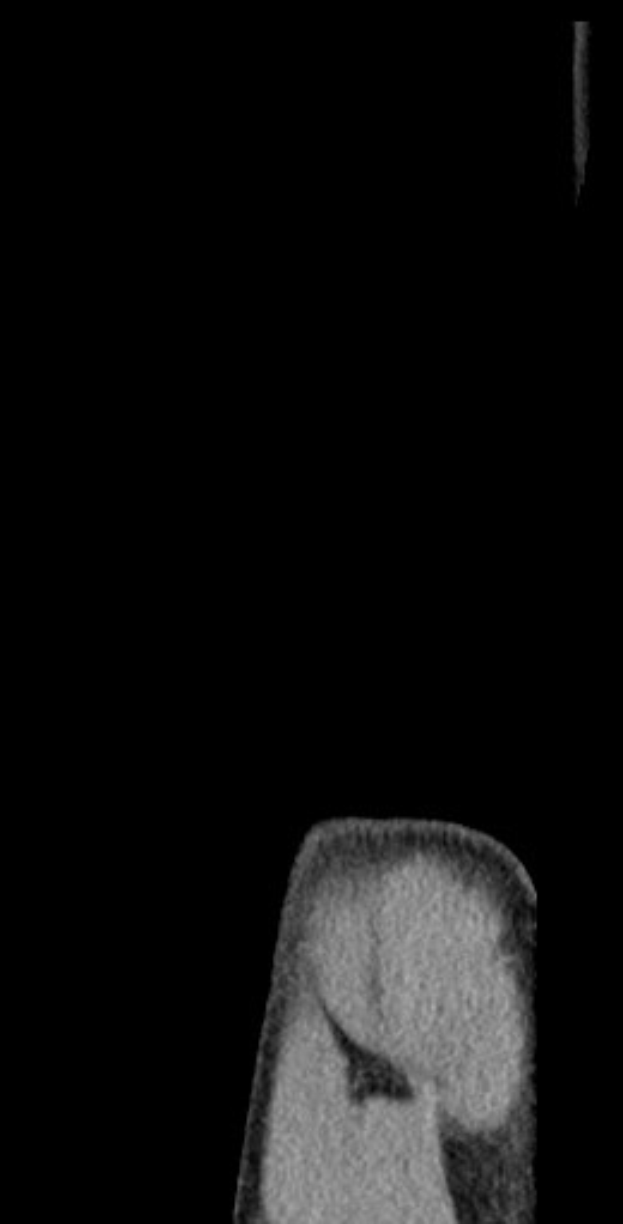

Der 22-jährige Linus Gechter, der erst kürzlich in den regulären Spielbetrieb zurückgekehrt war, musste das EM-Qualifikationsspiel der deutschen U21 gegen Griechenland vorzeitig mit Schulterbeschwerden verlassen. Nun steht eine MRT-Untersuchung an, um das Ausmaß der Verletzung zu klären. Sein Verein, der angesichts von Gechters Verletzungsgeschichte ohnehin bereits besorgt ist, wartet gespannt auf die Ergebnisse – besonders mit Blick auf das wichtige Heimspiel gegen Dynamo Dresden am Samstagabend (20:30 Uhr MEZ, live auf RTL Nitro und Sky).

Gechters Schulterprobleme begannen bereits in der letzten Saison, als ein Zusammenprall mit Teamkollege Deyovaisio Zeefuik ihn monatelang außer Gefecht setzte. Eine Operation im September 2024 hielt ihn auch zu Saisonbeginn von den Plätzen fern, doch der Innenverteidiger kämpfte sich zurück und entwickelte sich in der Rückrunde der 2. Bundesliga zu einer festen Größe in der Startelf.

Sein jüngstes Problem trat während des U21-Qualifikationsspiels gegen Griechenland auf, als ihn die Schmerzen zu einem frühen Wechsel zwangen. Da eine sofortige Diagnose aussteht, hat Hertha BSC vorsorglich eine MRT-Untersuchung angesetzt. Die Situation kommt denkbar ungünstig: Die Mannschaft bereitet sich auf das entscheidende Duell gegen Dynamo Dresden vor, das am Samstag um 20:30 Uhr im Berliner Olympiastadion angepfiffen wird.